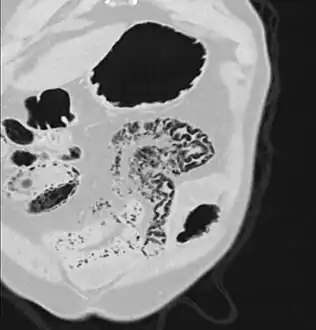

Pneumatosis intestinalis at computed tomography in intestinal ischemia. Lung window for better representation of the gas deposits in the intestinal walls. Coronal reconstruction.

Pneumatosis intestinalis in computed tomography with intestinal ischemia. Lung window for better representation of the gas deposits in the intestinal walls.- Upright AP radiograph showing gas in the wall of the small bowel in the left upper quadrant indicative of pneumatosis intestinalis.